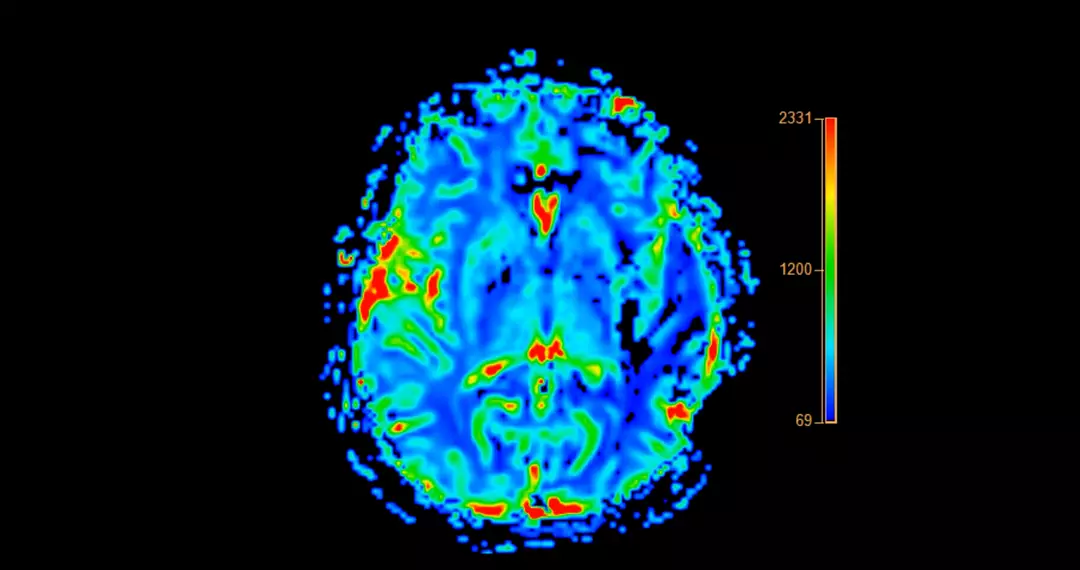

Doctors conducted thorough evaluations to identify the root cause of these symptoms, leading to the 19-year-old being diagnosed with probable Alzheimer’s disease.